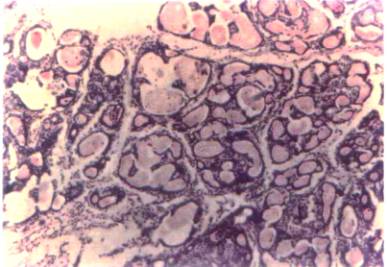

FOTOGRAFIA

3 Lesión pretumora1 pretumoral. Se puede observar

el marcado aumento en el diámetro

de los ductos y abundante secreción.

80x

FOTOGRAFIA 4 Hiperplasia, se pueden observar a mayor aumento las imágenes de la fotografía superior. La capa de células que rodea los ductos no presenta mayores alteraciones. 320 X